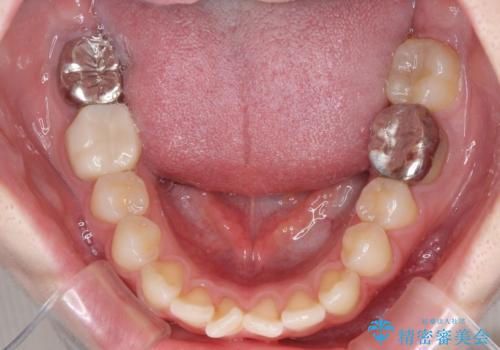

- 上下歯列全体のデコボコを気にして来院された患者様です。

主に下顎歯列全体の後方移動とIPR(歯と歯の間を削る)によってデコボコが解消するように設計し、インビザラインにより治療を行うこととしました。

1年半程度で終了するのではないかと予想しましたが、途中1年以上の来院がなく、トータルで3年の時間がかかってしまいました。

前歯のデコボコはより改善することが望ましい状態でしたが、患者様の希望により終了することとなりました。